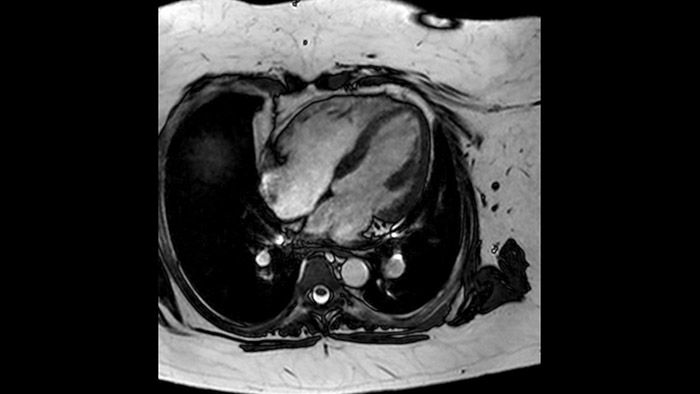

Diagnostic and prognostic utility of cardiac MR is increasing. Assess the anatomy and function of the heart using cine acquisitions, acquire information about perfusion and viability of the cardiac tissue, visualise potential edema with black blood sequence, access and even quantify tissue characterisation with CardiacQuant.